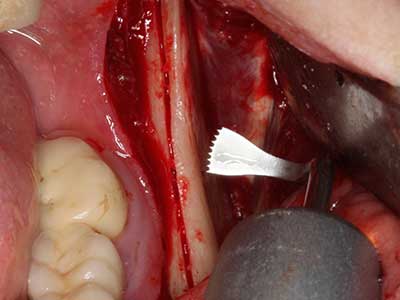

Fig. 18: Preparation of a cortical cover with the piezo bone saw (Piezomed, W&H).

Fig. 19: Surgical site after neurolysis and removal of osteoma.

Fig. 20: The removed bone cover is re-adapted and fixed with an osteosynthesis screw (KLS Martin, Tuttlingen).

When surgical procedures are performed on bone in the immediate vicinity of sensitive structures such as blood vessels or nerves, rotary instruments pose a significant risk of iatrogenic injury. Piezoelectric devices can be helpful for preparation of bone covers and removal of hard tissue close to nerves, particularly for exposure of nerves after iatrogenic injury but also during nerve lateralization for resective and reconstructive procedures or implant placement (Fig. 17-20). Light contact between the piezotip and the nerve does not generally result in damage but proceeding incautiously with saw-like motions or attachments where a residual bone substrate remains may cause temporary or even permanent nerve damage. However, the risk of damage is considered to be substantially lower than when using saws or milling instruments (Pereira, Gealh et al. 2014).